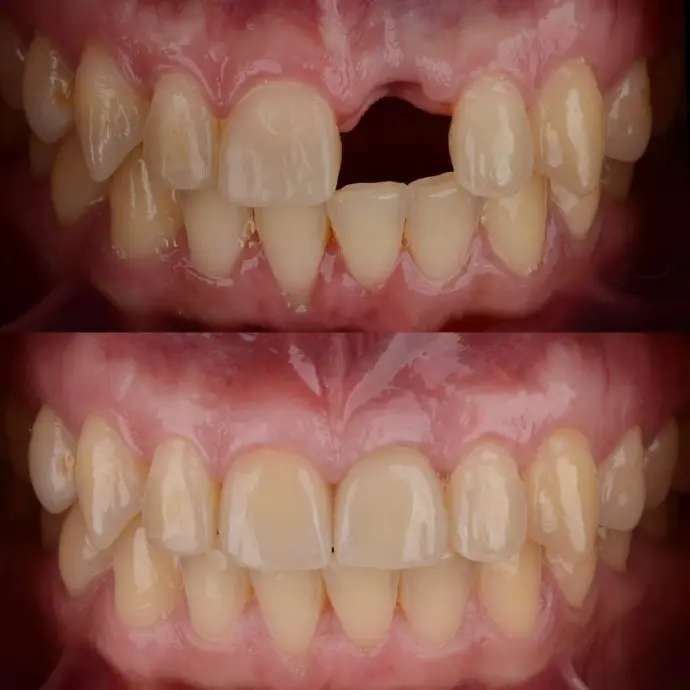

Missing a tooth affects everything, from chewing to confidence to long-term oral health. A single dental implant restores your smile with a strong, natural-looking tooth that blends perfectly with your real teeth.

Beautiful, natural appearance in photos and daily life

Look and feel like a natural tooth

Yes. The crown is custom-shaded and shaped to blend seamlessly with your smile.